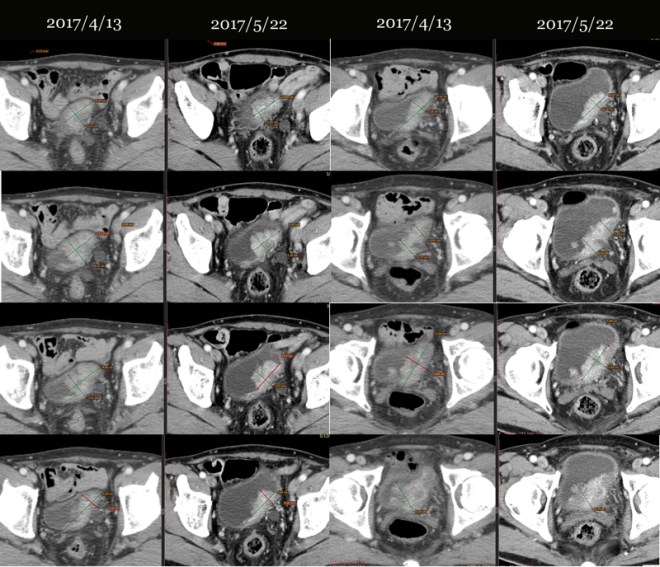

이 환자는 2017년 5월 31일 방사선 치료 전에 찍은 CT 사진을 가지고 왔다. 그래서  오늘 상담을 하고 이전 최초 발견한 2017년 4월 13일과 한방치료를 한달 가량 받고 아직 방사선 치료를 시작하기 전인  2017년 5월 22일 사진을 비교하였다. 내가 방사선 전문가가 아니기 때문에 전체 체적을 볼 수는 없고, 단지 CT 상 같은 부위를 불규칙한 방광을 침범한 종양의 두께를 재어서 비교를 하였다. 그리고 이는 나의 clinic에서 사용한 한약이 방광에 어떠한 영향을 주었는가를 알 수 있는 자료이다. 독자들은 참고 하시기 바란다.

이장호비교.jpg